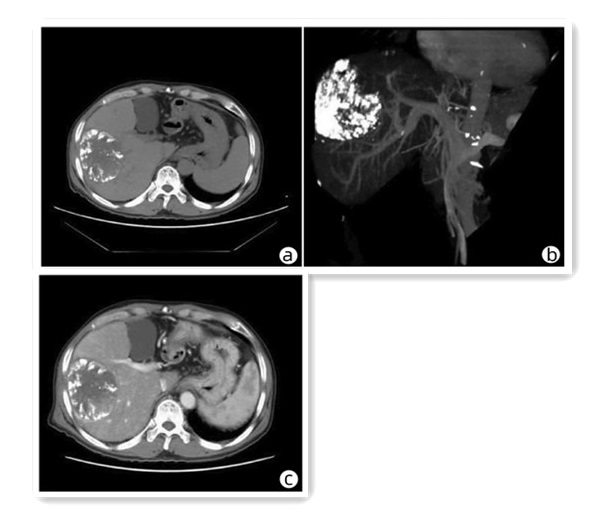

骨髓增生性疾病所致门静脉海绵样变性1例报告

韩冰, 涂传涛

2023, 39(6): 1414-1417. DOI: 10.3969/j.issn.1001-5256.2023.06.025

摘要(805) HTML (260) PDF (2374KB)(48)

摘要: